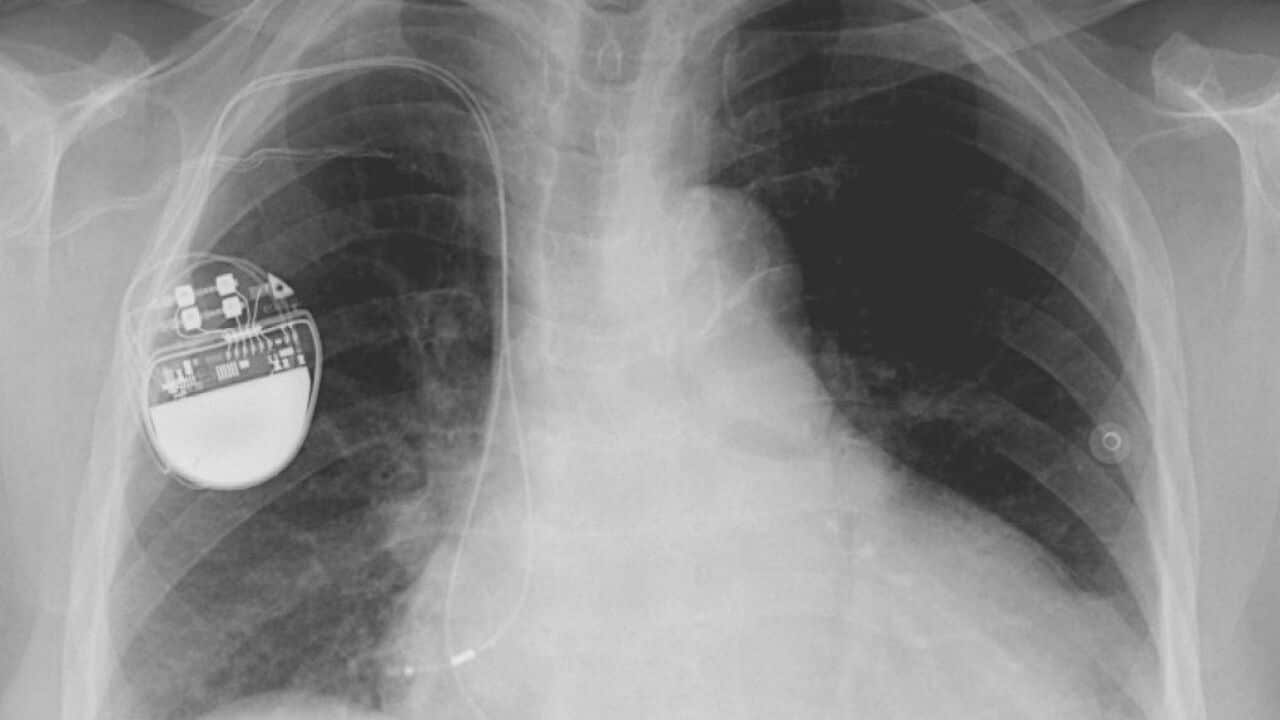

Faulty medical devices have reportedly been used widely due to lax regulation in Europe, a lack of transparency, and poor regulation. Source: Supplied

Natuklasan sa isang pang-daigdigang imbestigasyon na ang mga di-gumaganang pangmedikal na implant ang may kagagawan sa libu-libong kamatayan sa mundo.